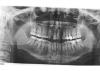

Заринка Опубликовано 12 октября, 2013 Поделиться Опубликовано 12 октября, 2013 (изменено) Мне 29 лет и у меня было 2 молочных боковых резца на верхней челюсти. Сохраняла как могла, но увы... один сломался. Проконсультировавшись с доктором, было принято решение сделать синус-лифтинг, т.к. кость атрофировалась и установить 2 импланта. В мае была проведена операция. По прошествии 4-х месяцев был сделан снимок, который показал, что на левой стороне кость сформировалась не так как нужно, но возможность установки есть, просто имплант будет поставлен чуть выше второго (со слов доктора) и 24.09.2013г. мне установили импланты. С этой стороны уже сейчас видно как ушла десна, смотрится очень не красиво. Можно ли это как то исправить? и на каком этапе?Заранее спасибо. Изменено 12 октября, 2013 пользователем Заринка Ссылка на комментарий

red_butler Опубликовано 14 октября, 2013 Поделиться Опубликовано 14 октября, 2013 Снимки не получилось пока взятьСделайте новые rg и более качественные фотоснимки, без этого - "гадания на кофейной гуще" Ссылка на комментарий

Bier Опубликовано 18 октября, 2013 Поделиться Опубликовано 18 октября, 2013 скорее всего там инфицирована поверхность имплантата. Сделайте КТ, судя по всему он частично не в кости. 1 Ссылка на комментарий